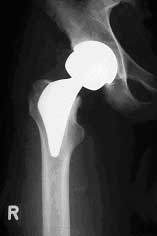

Proxima® Schaft der Fa. DePuy mit Röntgen